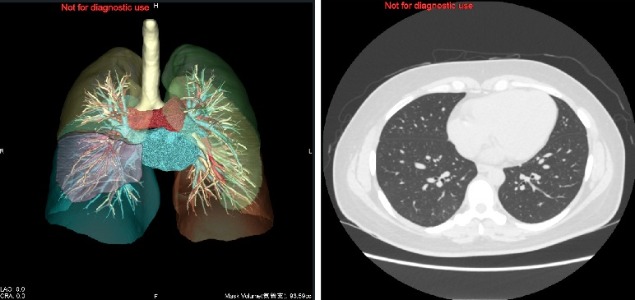

当院の人間ドックでは、肺がん等の早期発見を目的とした「肺がんドック」をオプションとして2001年4月から実施していますが、新しいCT機器の導入に伴い期間限定で同機により可能な3D画像(通常5千円程度)を無料でお付けするプラン「プレミアム肺がんドック」を実施いたします。

320列マルチスライスCTを使うので、胸部をらせん状に隙間なく短い時間で撮影が可能です。また、1ミリ間隔で撮影しますので、通常の胸部X線撮影では、見つかりにくい直径数ミリのごく小さな初期の肺がんを見つけだすことが可能となりました。

・マルチスライスCTによるX線撮影

(1.25mm間隔で画像を撮影します。併せて3D画像を作成します。)

期間限定特別企画で撮影した肺の3D 画像を無料(通常5千円程度)でご提供!!